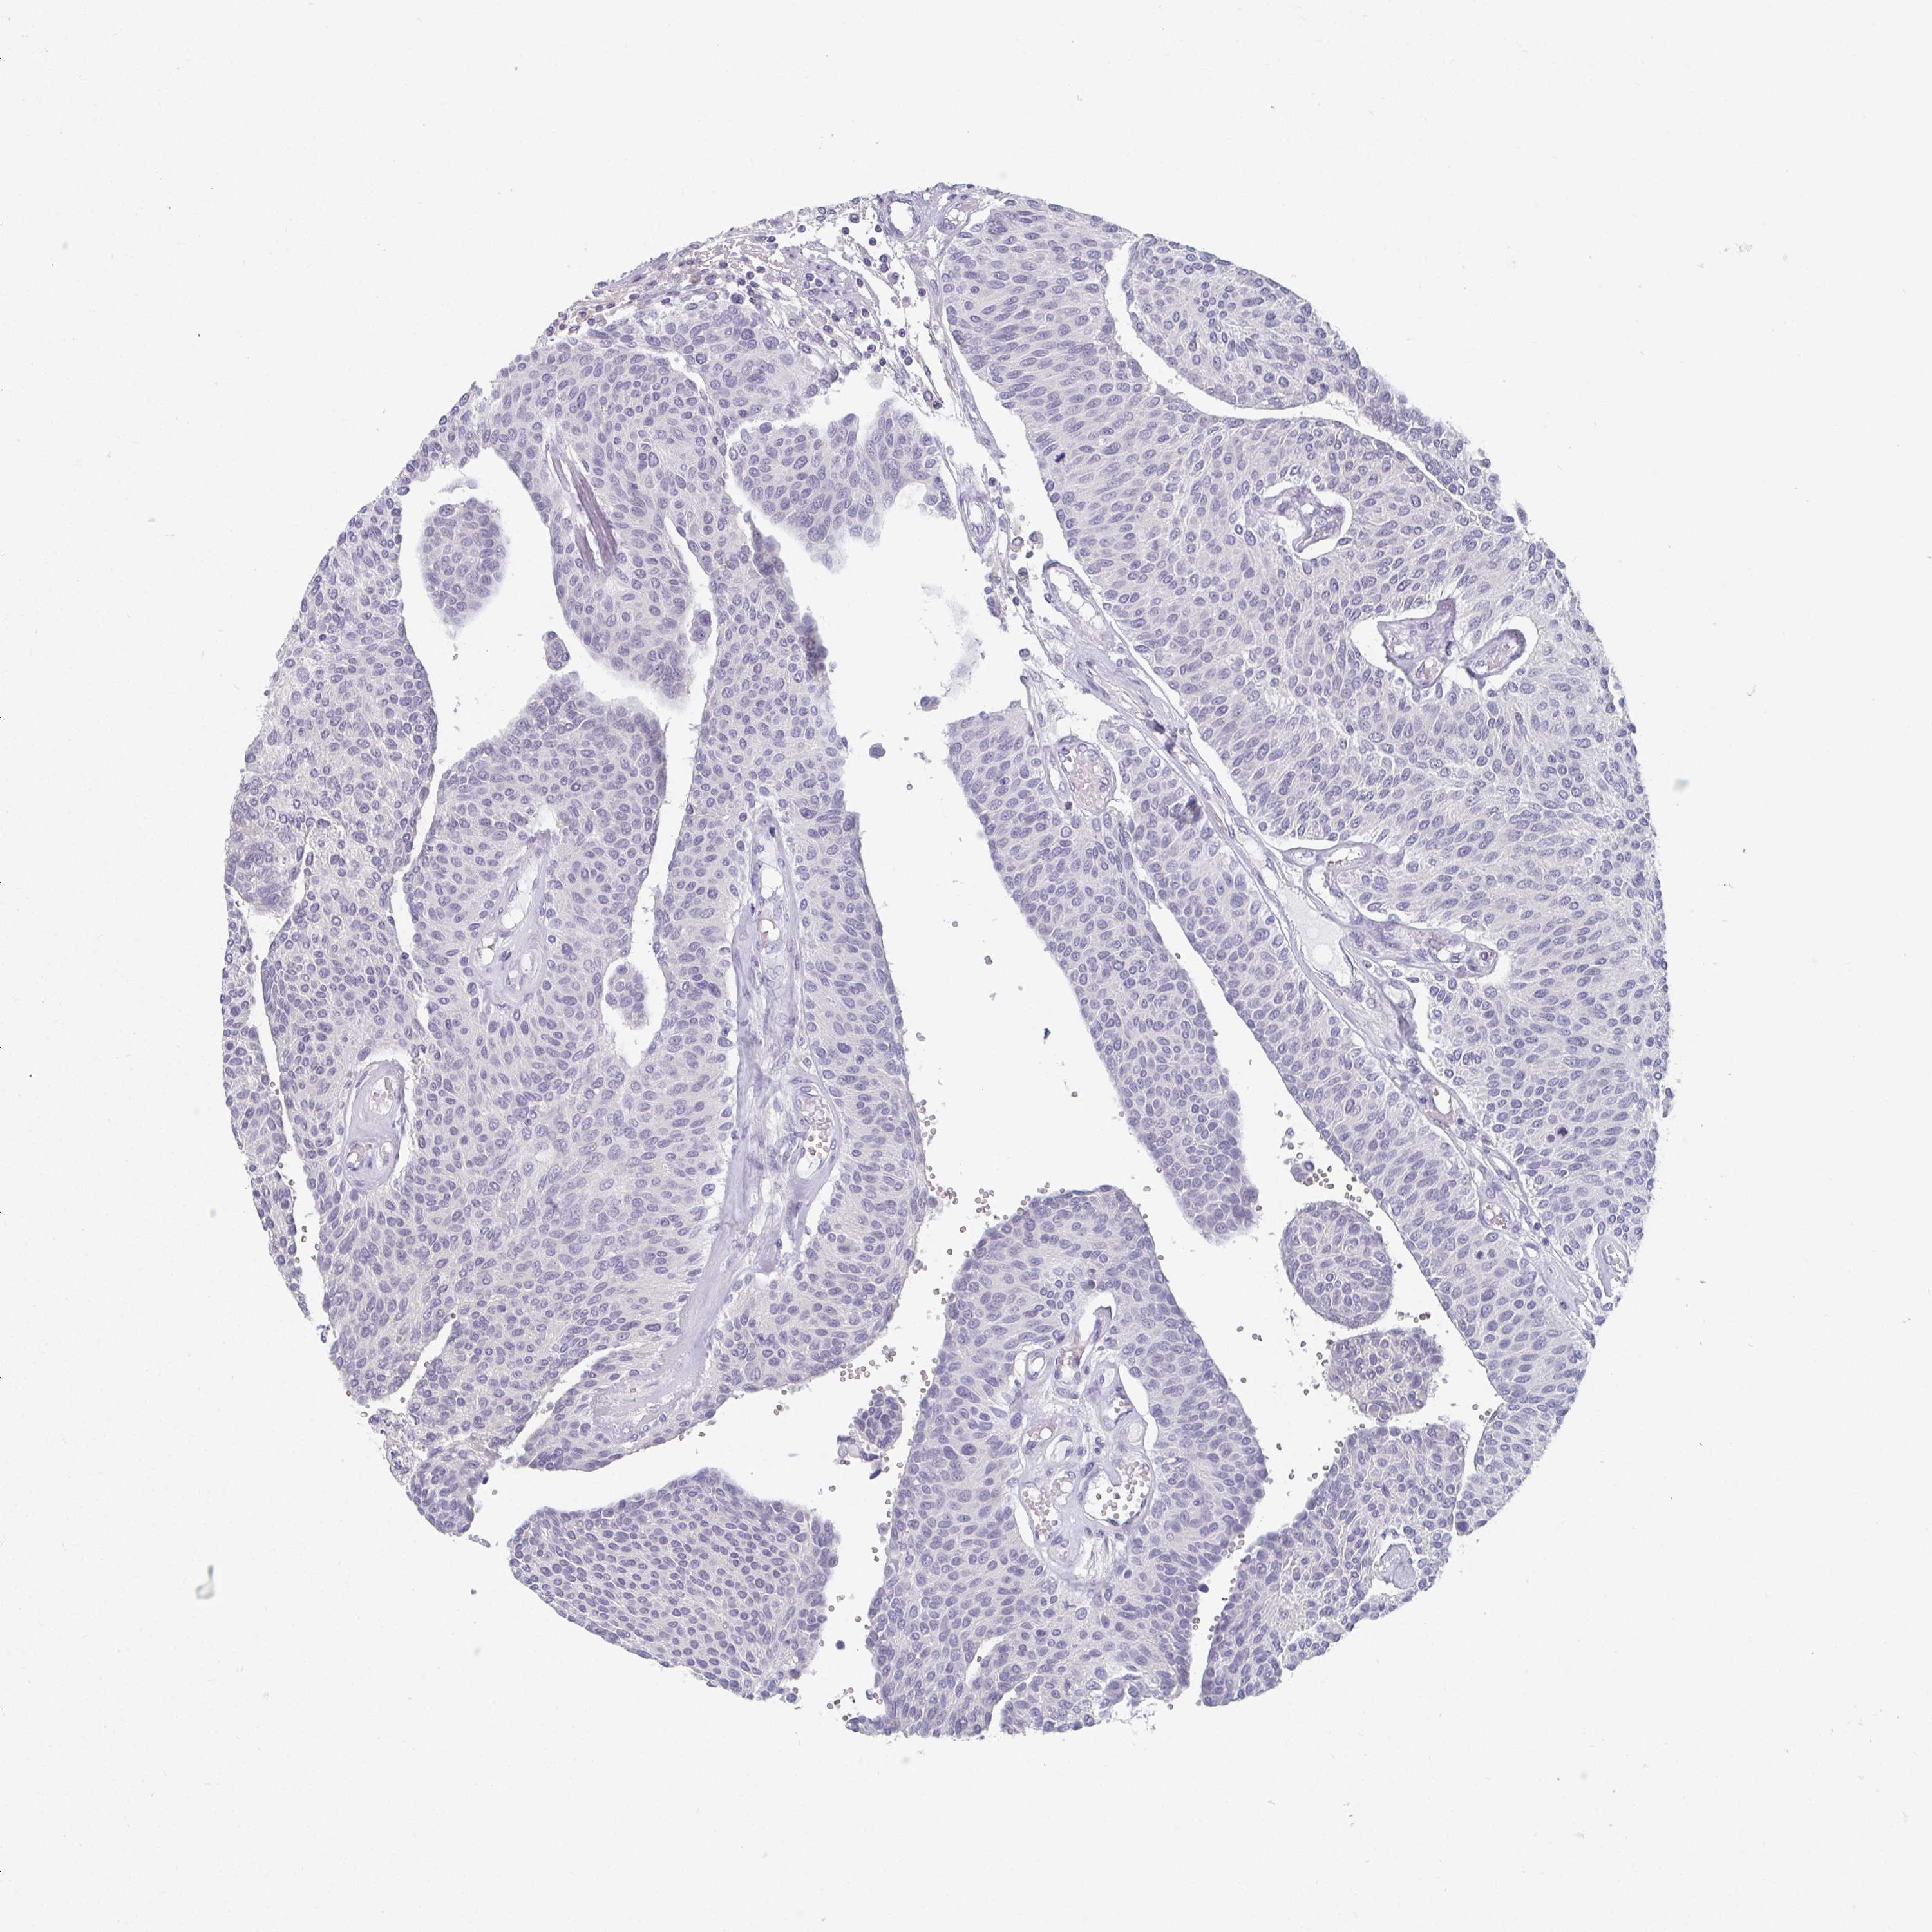

UROTHELIAL CANCER - Protein expressioni

A mouse-over function shows sample information and annotation data. Click on an image to view it in a full screen mode. Samples can be filtered based on level of antibody staining by selecting one or several of the following categories: high, medium, low and not detected. The assay and annotation is described here.

Note that samples used for immunohistochemistry by the Human Protein Atlas do not correspond to samples in the TCGA dataset.

Antibody stainingi

Antibody staining in the annotated cell types in the current human tissue is reported as not detected, low, medium, or high, based on conventional immunohistochemistry profiling in selected tissues. This score is based on the combination of the staining intensity and fraction of stained cells.

Each image is clickable and will lead to virtual microscopy that enables deeper exploration of all samples and also displays staining intensity scores, fraction scores and subcellular localization as well as patient and tissue information for each sample.

Antibody HPA007656

Antibody CAB034931

Urothelial carcinoma, High grade

Urothelial carcinoma, NOS

Urothelial carcinoma, Low grade